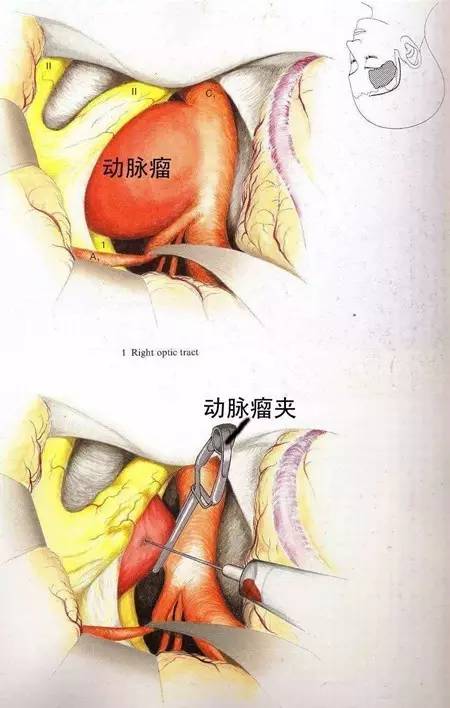

颅内动脉瘤的治疗:

1、直接手术,其中瘤颈夹闭是最好的方法。

2、间接手术,结扎颈部动脉,此种方法风险大。